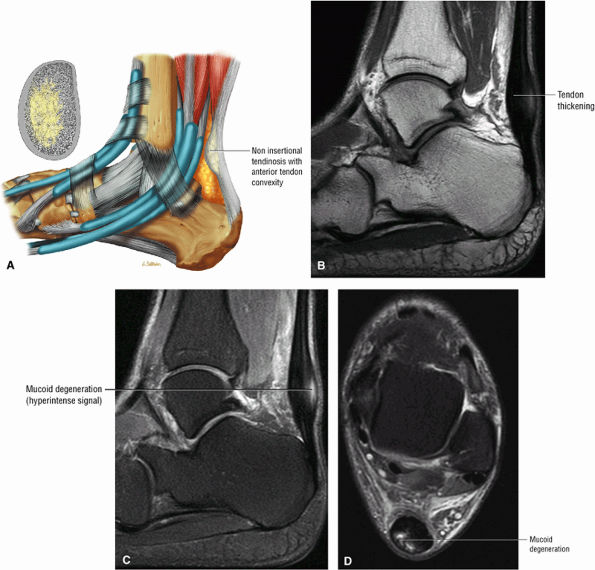

Tendinitis or tendinopathy represents intrasubstance tendon degeneration.

Achilles tendinitis is subdivided into non-insertional tendinosis and insertional tendinitis.

MR identifies nodular or convex tendon thickening and intratendinous mucoid degeneration.

In tendinosis or tendinopathy, there is intrinsic or intrasubstance degeneration of the Achilles tendon.

-

Increased cross-sectional diameter on axial images

Increased anteroposterior dimensions

Prominent anterior convexity with focal or diffuse thickening in the sagittal plane

Thickening and intermediate signal of peritendinous tissue dorsal, medial, and lateral to the Achilles tendon on T1- or PD-weighted images

Intermediate-signal-intensity effacement of peritendinous tissue anterior to the Achilles tendon on T1- or PD-weighted images

Hypointense to intermediate signal within an enlarged tendon in hypoxic fibromatosis (Fig. 5.111) on FS PD FSE images

Inflammatory fluid anterior to the tendon and proximal extension of fluid in the retrocalcaneal bursa

Myxoid degeneration (Fig. 5.112) with increased signal on FS PD FSE or STIR images

Calcific (Fig. 5.113) or ossific degeneration with tendon thickening

Associated partial tears